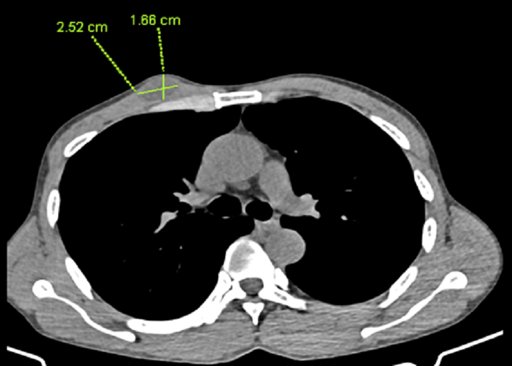

3 tháng trước khi đi khám, nam bệnh nhân (53 tuổi, ở Hà Nội) xuất hiện nuốt vướng, khàn tiếng và sụt cân. Do các dấu hiệu đó tăng dần, bệnh nhân đi khám vô cùng bất ngờ với chẩn đoán mắc bệnh ung thư nguy hiểm ở giai đoạn IVB.